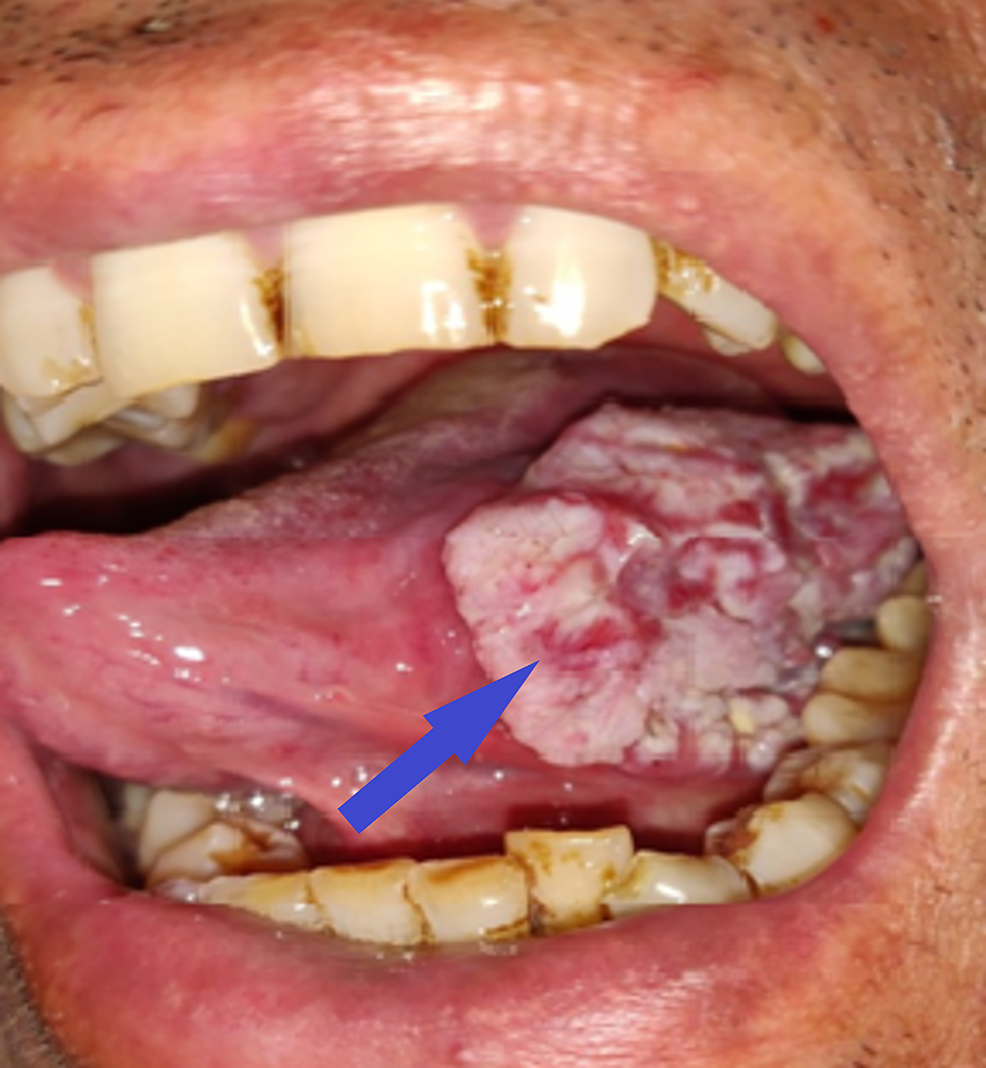

Cancer may occur sporadically or may have a genetic predisposition. However, environmental risk factors also play a pivotal role. Following cancers are strongly associated with smoking: - lung cancer - laryngeal carcinoma - oral cancer - esophageal carcinoma - bladder carcinoma - renal cancer - liver cancer - stomach cancer - pancreatic carcinoma - colon cancer - cervical cancer - acute myeloid leukemia - rectal cancer Reference: https://www.cancer.gov/about-cancer/causes-prevention/risk/tobacco#:~:text=Tobacco%20use%20causes%20many%20types Image via: https://www.cureus.com/articles/65563-tongue-cancer-in-a-young-male